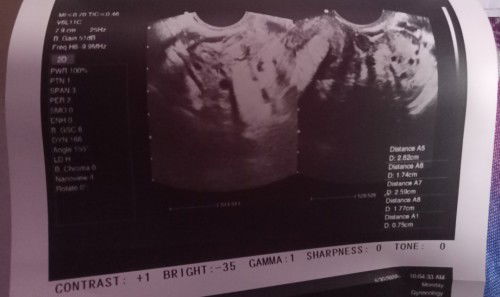

Asking for my friend po Bali nagpatransv v po Kasi siya tapos Wala Naman po sinabi Yung doctor na nagtrans v sakanya ob kona daw Po mag eexplain Pagdating Naman po kay ob Sabi Po sakanya possible may pcos daw po siya pero payat Naman po Yung kaibigan po. Kaya medyo nagtataka po kami tapos nagpositive din Po Kasi siya sa pt non. Sabi ni ob po baka daw po early pregnancy pa lang daw po pinababalik po siya uli Ng ob para magpatrans v after ilang weeks nandiyan po Yung result at remarks Nung doctor medyo naguguluhan na po Kasi kami . Pinagtake po siya Ng folic acid#advicepls

Normal po ba ba magspotting? Ang buntis? Ang akin po Kasi simulang June 27 park lang siya as in parang brown pa Yung kulay hanggang kahapon Ng june 28 patak parin siya. Tapos ngayon pero pa din Po parang light pink po siya di gaano kadami pero di na Po siya patak parang tubig po. Nagpt po Kasi kami Ng ob ko positive po. Pero nagbleedinh din po Ako non while nagpt kami peor positive. s pero bago po ako magpt sa ob nagtry din Po ako Nung may negative naman. Nag patrans v na din po Ako last month nakalagay po namamaga matres ko suggest po Ng ob ko magtake ako Ng dusthapon at folic acid Kasi baka daw po early pregnancy #1stimemom #pleasehelp #pregnancy #firstbaby

Normal po ba ba magspotting? Ang buntis? Ang akin po Kasi simulang June 27 park lang siya as in parang brown pa Yung kulay hanggang kahapon Ng june 28 patak parin siya. Tapos ngayon pero pa din Po parang light pink po siya di gaano kadami pero di na Po siya patak parang tubig po. Nagpt po Kasi kami Ng ob ko positive po. Pero nagbleedinh din po Ako non while nagpt kami peor positive. s pero bago po ako magpt sa ob nagtry din Po ako Nung may negative naman. Nag patrans v na din po Ako last month nakalagay po namamaga matres ko suggest po Ng ob ko magtake ako Ng dusthapon at folic acid Kasi baka daw po early pregnancy #1stimemom #advicepls #pleasehelp #pregnancy .